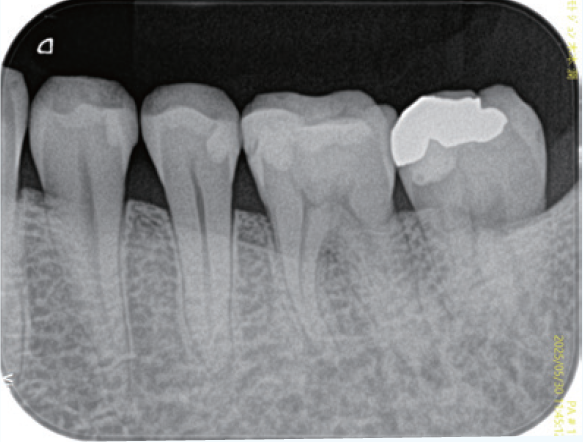

「臨床症例1」下顎左側第一大臼歯の咬合痛を主訴に来院

●年齢30代 男性

歯髄反応(―)であったため歯髄壊疽と診断し根管処置を行なった。根管口付近にある器具操作するには規制になるような形態に対して修正形成を行い、ファイルの根尖への到達性を確保して、根尖付近の根管拡大・形成を的確に行うため適正と思われるテーパーを付与し根管充填を行なった。根管充填材は根尖周囲組織にも炎症が疑われる透過像が認められていたため、より根尖周囲組織の殺菌・抗菌効果を得るために歯科材料として生体に為害作用が少ないと承認された歯科材料承認ClassⅢのシーラーを使用した。適正に根尖部にテーパーが付与できたため根尖周囲部の開口部に根管充填材が行き渡り、根尖部の封鎖が良好な結果が得られた。

<術前>

覆髄材が近心髄角部付近まで充填されていて慢性の刺激により歯髄腔の狭窄が見られる。近心根根管口付近は遠心方向への規制があり、器具の根尖部への到達性を妨げている。

<術後>

近心根の根管口付近は湾曲度の修正形成が行われ、比較的緩やかな湾曲根管の処置になった。遠心根は根管口から根尖部まで連続したテーパーが付与され、根管充填時のプラガーの圧は適正に伝わり、根尖付近の複数の開口部に根管充填材が行き渡っていることが確認できる。